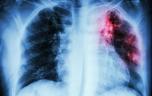

Tuberculose : une des maladies contagieuses les plus meurtrières

SIphotography / iStock